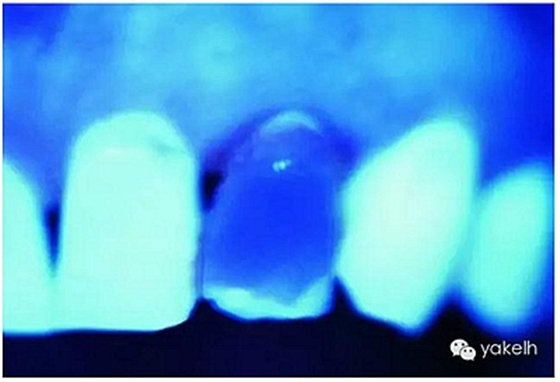

圖2.30,圖2.31通過紫外線光照下的天然牙齒,顯示牙齒的熒光性。

天然牙暴露在紫外線光下顯示熒光,通常是白色淡藍(lán)色的色調(diào)(藍(lán)白色)[13,22]。由于有機(jī)物的存在,以及大量有機(jī)物色素對(duì)紫外線光譜的感光性,牙本質(zhì)是產(chǎn)生熒光的主體,比牙釉質(zhì)的熒光更強(qiáng)烈。

有研究表明,天然牙和天然蛋白質(zhì)的熒光很可能是從氨基酸苯丙氨酸結(jié)合物和酪氨酸色氨酸引起的能量轉(zhuǎn)移所導(dǎo)致。牙本質(zhì)比牙釉質(zhì)顯示出更高程度的熒光性,釉質(zhì)的熒光性非常低,礦化程度的增高,導(dǎo)致熒光性降低。熒光隨著牙本質(zhì)脫礦而增加,這解釋了為什么釉質(zhì)作為高度礦化組織,相對(duì)于牙本質(zhì)表現(xiàn)出非常低的熒光性的原因。